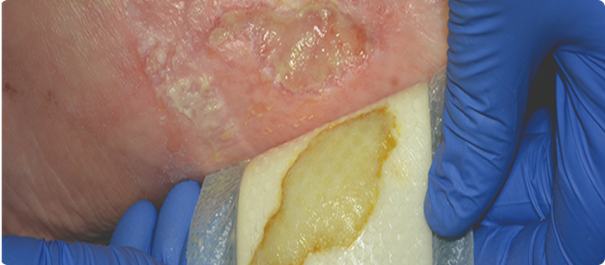

La quantité d’exsudat, ou liquide de la plaie, augmente pendant la phase inflammatoire. Cela permet de nettoyer la plaie et de créer un milieu humide qui optimise la cicatrisation. Cependant, si une plaie commence à sécréter trop d’exsudat, cela peut ralentir le processus de cicatrisation. Pour en savoir plus sur l’exsudat de la plaie et son traitement, lisez le présent article.